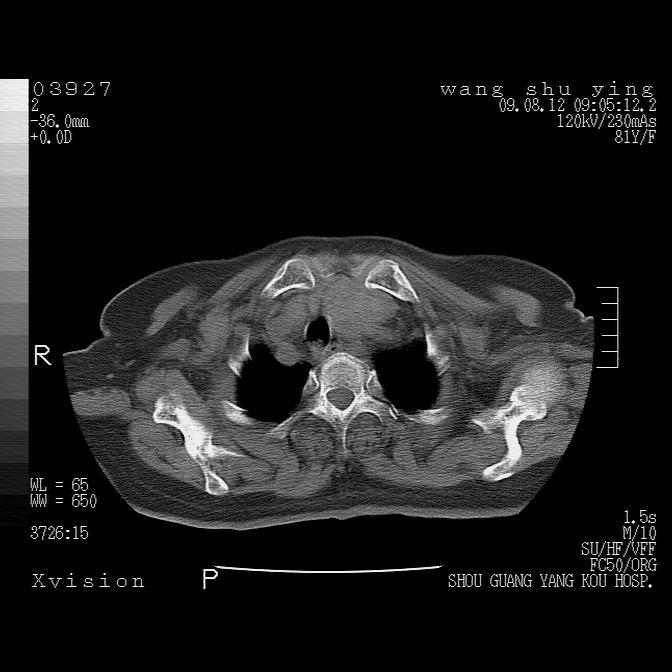

以下是引用帅河马在2009-8-12 12:59:00的发言:[br]两肺感染性病变伴双侧胸膜肥厚。[br]左侧甲状腺腺瘤不除外。[br]腹水+心包积液。[br][br][本贴已被 帅河马 于 2009-8-12 13:14:32 修改过]

以下是引用sdzyy在2009-8-12 18:17:00的发言:[br]两肺感染性病变伴双侧胸膜肥厚。[br]左侧甲状腺腺瘤不除外。[br]腹水+心包积液。[br]支持

以下是引用随光逐影在2009-8-12 19:42:00的发言:[br]1)两肺感染性病变伴双侧胸膜肥厚。2)不排除左侧甲状腺腺瘤。3)肝脏占位性病变;建议行进一步检查。